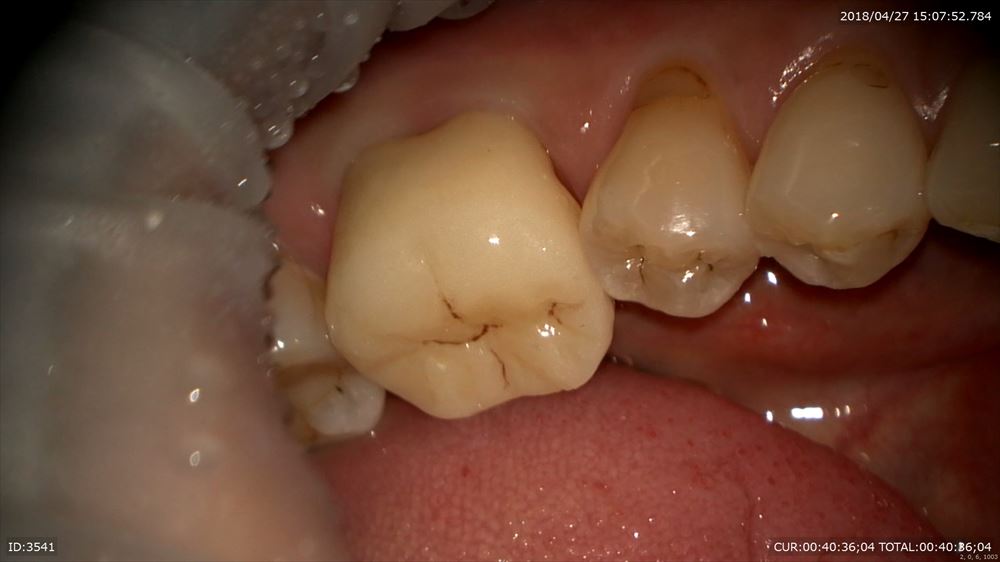

精密な型を採ったので完璧なフィッティング技工士間中先生の腕。いつも大変お世話になっております。

仮歯を外して

歯肉に炎症がない事を確認